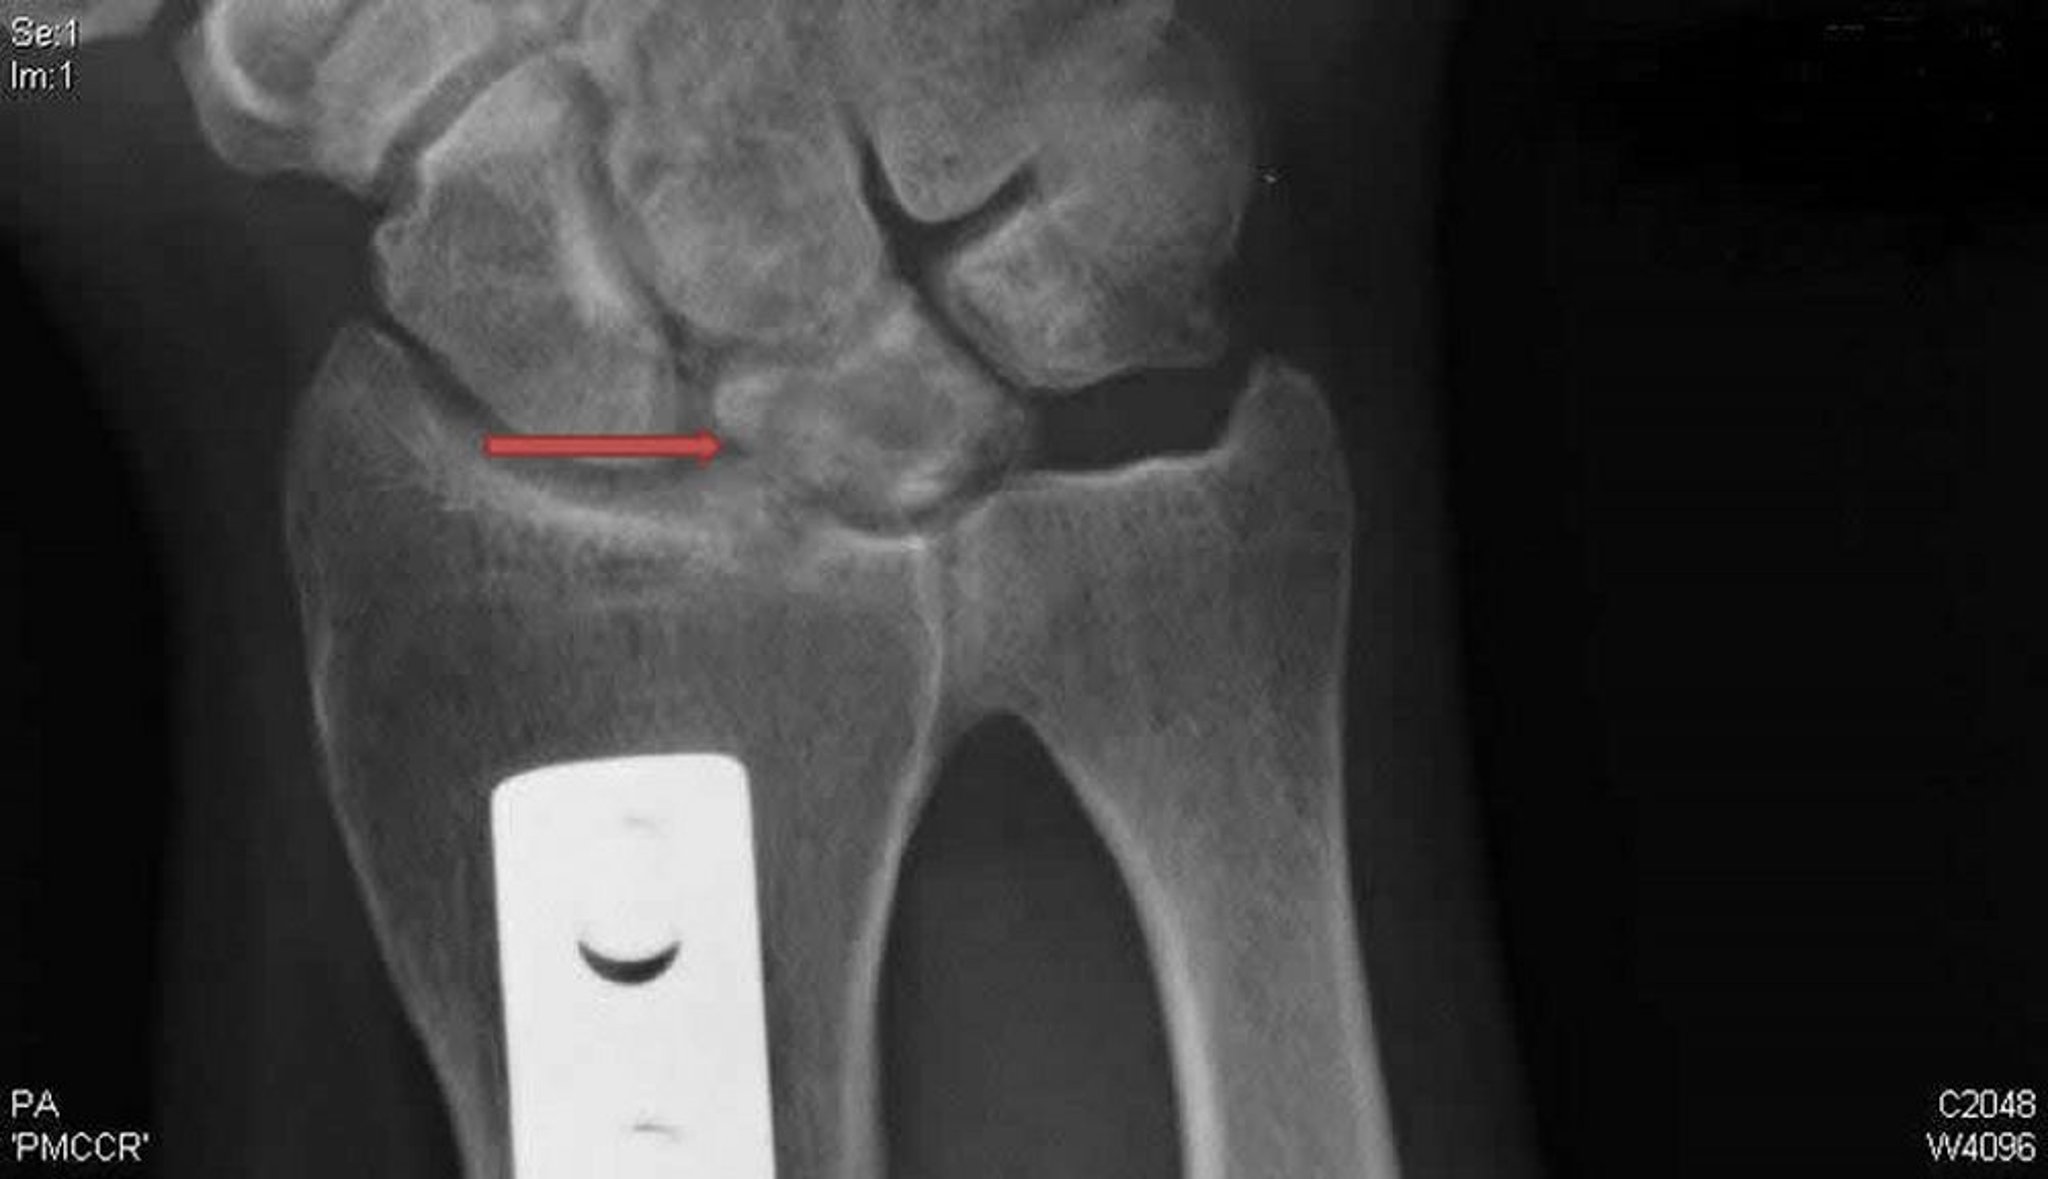

Kienböck-Krankheit (posteroanteriore Röntgenaufnahme)

Diese posteroanteriore Röntgenaufnahme des rechten Handgelenks zeigt Zysten und Sklerose des Os lunatum (Pfeil), die typisch für die Kienböck-Krankheit sind. Die Metallplatte ist ein Beweis für eine radiale Verkürzungsosteotomie, die in dem Bemühen durchgeführt wurde, das Lunatum zu entlasten und diesen Zustand möglicherweise zu behandeln.

X-ray courtesy of David R. Steinberg, MD.